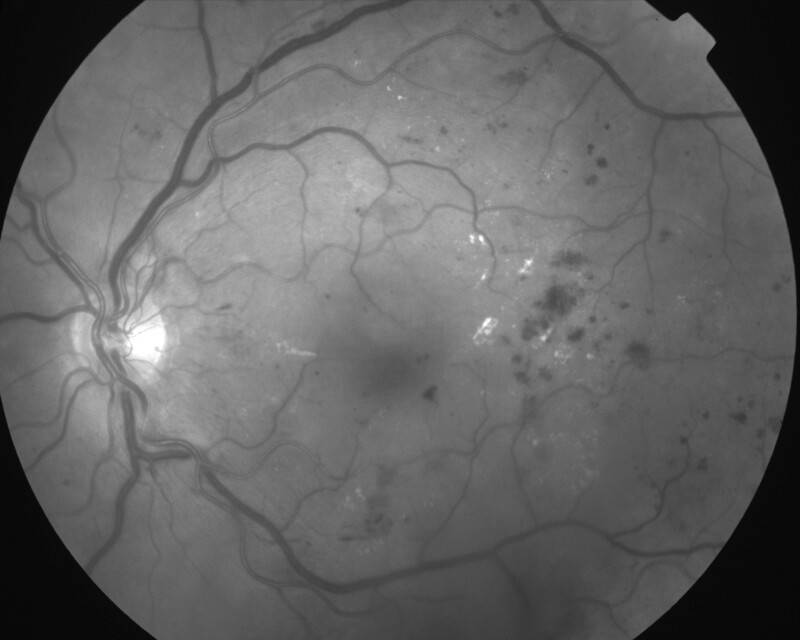

RETINOPATHIE DIABETIQUE PROLIFERANTE